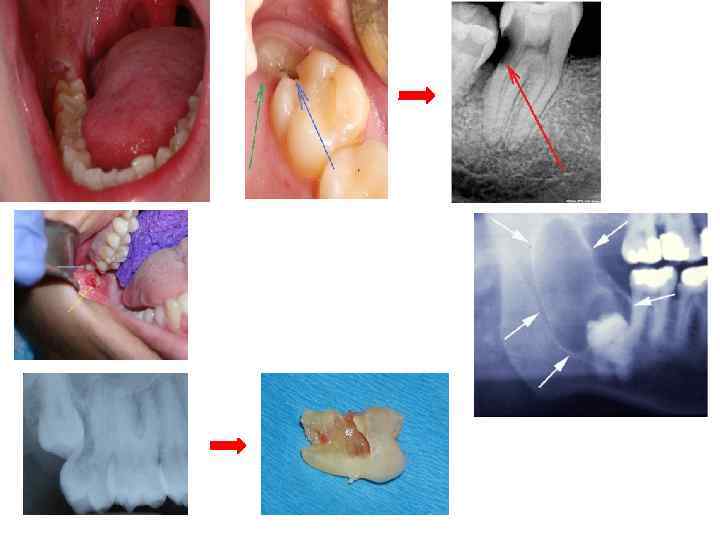

Методы визуализации Дентальная рентгенография — полуретенция, дистопия зуба 3. 8 Дентальная рентгенография —дистопия зуба 3. 8

Слизистая оболочка десны, которая частично покрывает коронку прорезывающегося зуба называется Капюшоном Воспаленный капюшон на обоих рисунках показан стрелочками.

Клиническая картина перикоронарита зуба 4. 8 — перикоронарэктомия: а — до проведения перикоронарэктомии; б — непосредственно сразу после проведе ния перикоронарэктомии